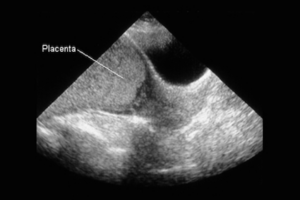

Los servicios de Ginecología y Obstetricia, y de Urología de esta sede médica detallaron que la paciente, quien se dedica a la docencia, fue diagnosticada con placenta previa total y percretismo placentario, dos condiciones en las que la placenta que envuelve al bebé no se adhiere en el lugar correcto durante el embarazo e invade las paredes del útero, lo que representaba un peligro para la vida de ambos ante la presencia de hemorragia masiva.

¿Qué es la placenta previa?

De acuerdo con un artículo publicado por Medline Plus, la placenta previa es un problema del embarazo en el cual la placenta crece en la parte más baja de la matriz (útero) y cubre toda la abertura hacia el cuello uterino una parte de esta:

“La placenta crece durante el embarazo y alimenta al feto. El cuello uterino es la abertura hacia la vía del parto”.

Existen diferentes formas de placenta previa:

- Marginal: La placenta está al lado del cuello uterino, pero no cubre la abertura.

- Parcial: La placenta cubre parte de la abertura cervical.

- Completa: La placenta cubre toda la abertura cervical.